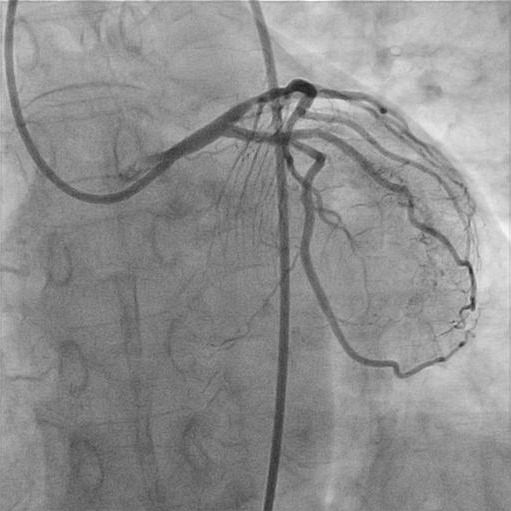

緊急冠動脈形成術(PCI)が行われ、同部位2箇所にステントが留置されました。

緊急冠動脈形成術(PCI)後の画像

患者さんの症状は急速に改善、処置が終了し病室に帰室されました。 心電図の経過をみると、

変化は明らかですが、その後、心筋逸脱酵素の上昇もなく心筋梗塞は回避できたと考えています。